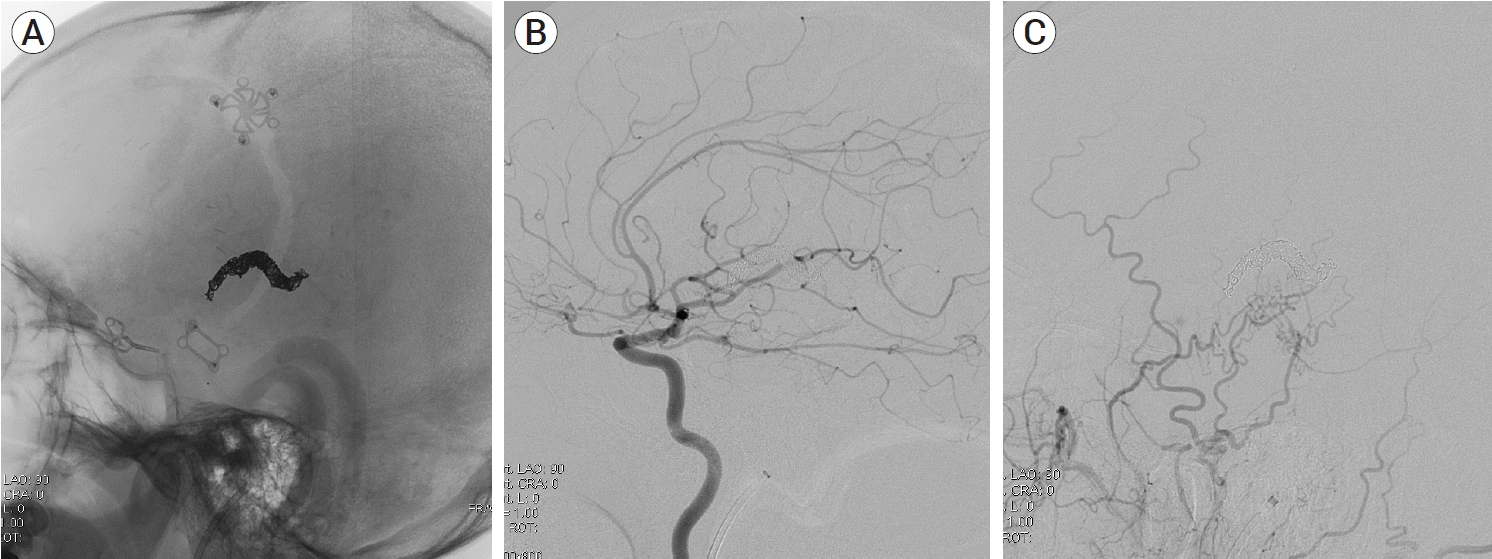

Fig. 1.

(A) Contrast-enhanced computed tomography (CT) scan showing venous ectasias beneath the previous left craniotomy site (black arrow). (B) Three-dimensionally reconstructed CT angiography demonstrating suspicious dual arteriovenous fistula with multiple feeders from pial arteries (black arrow) and dural arteries (white arrow). Cortical venous reflux and venous hypertension is suspected (arrowhead).